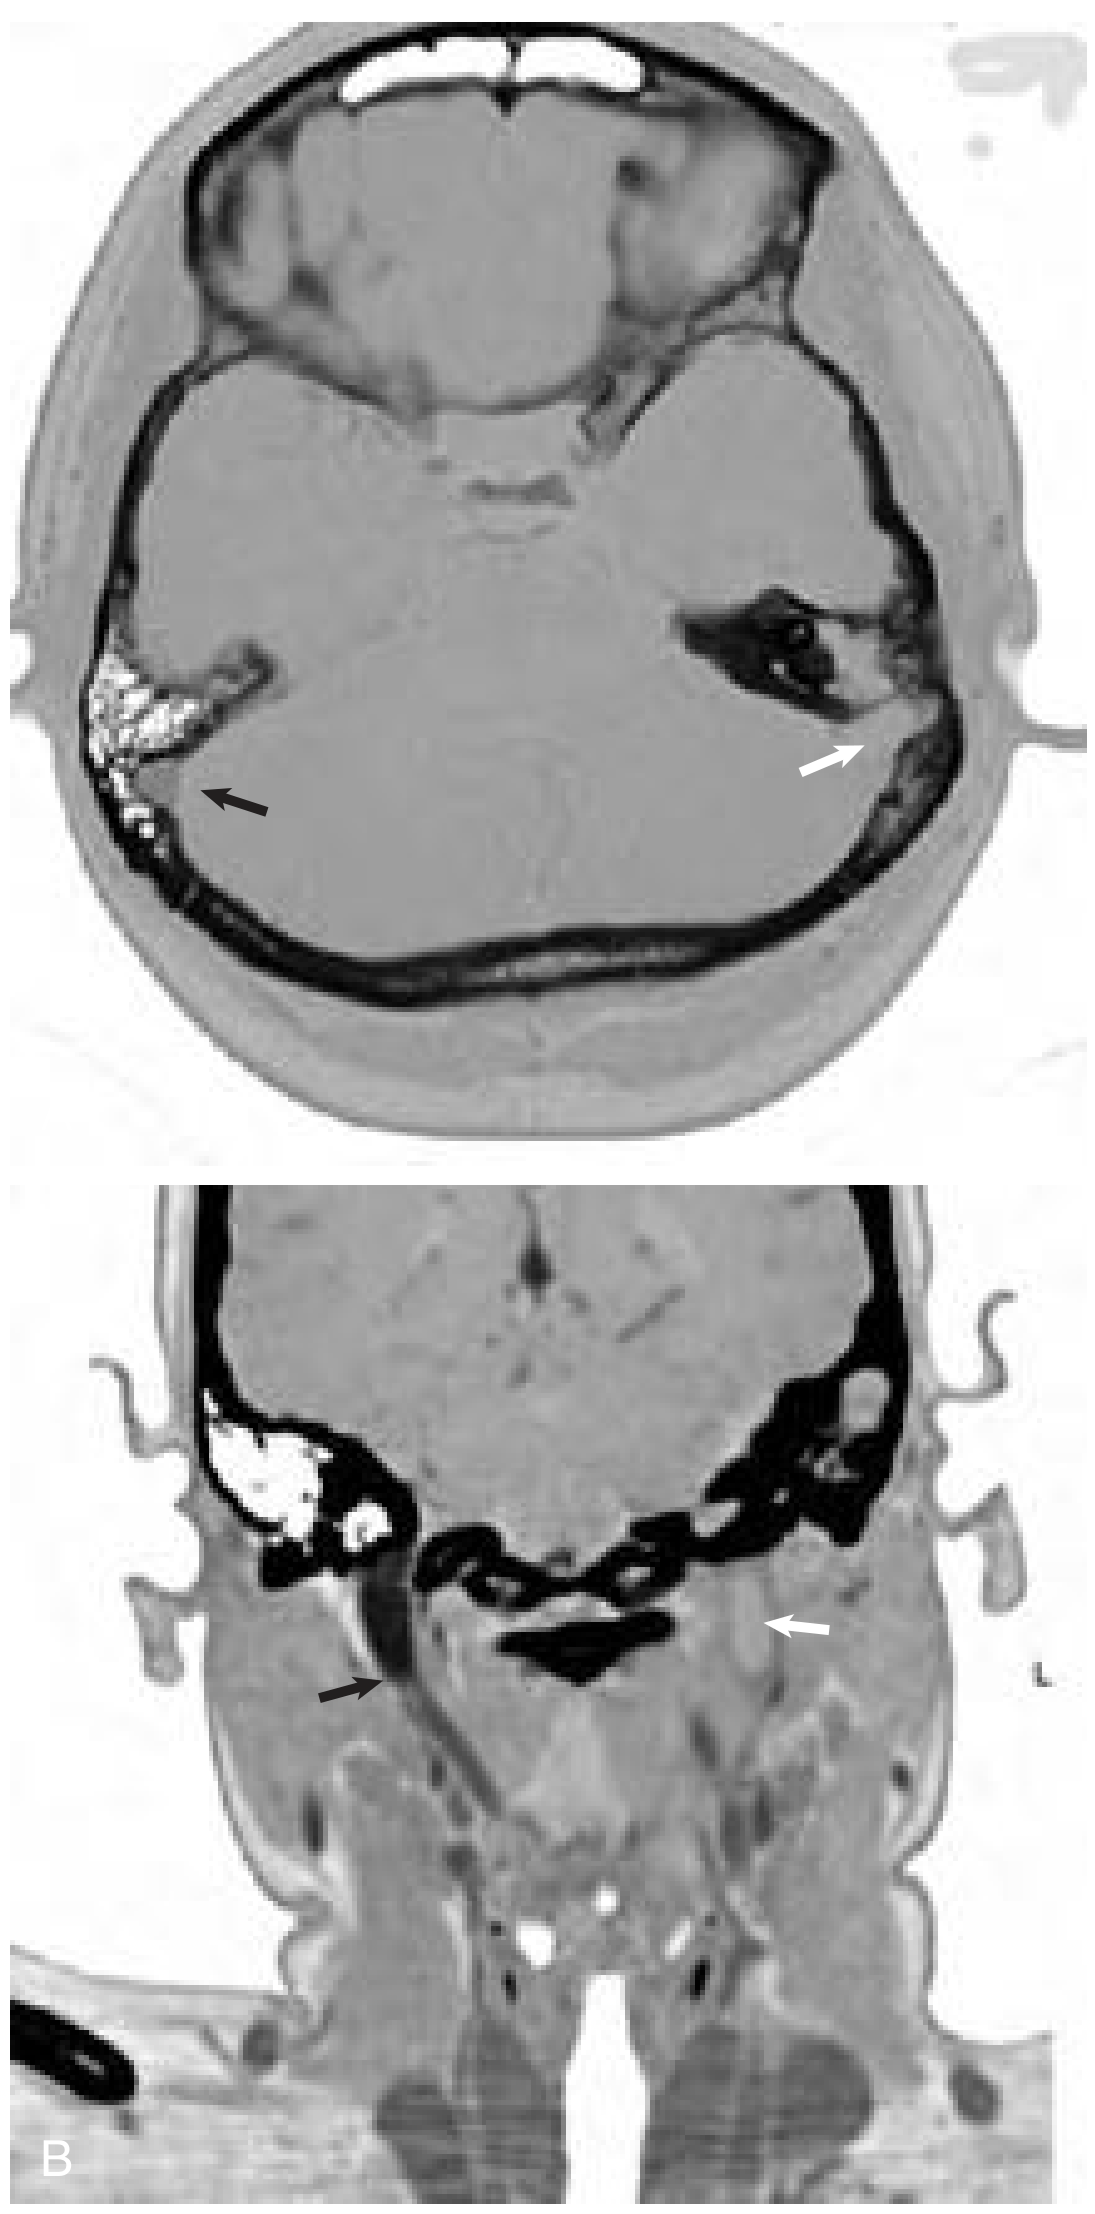

1. CT Scan (Contrast-Enhanced Temporal Bone CT):

The "Delta sign" (Empty triangle sign / Empty delta sign):

• Absent enhancement of the sigmoid sinus (compared to normal opposite side)

• Opacified mastoid air cells

• May show perisinus abscess

CT scan showing absent enhancement of left sigmoid sinus (white arrow) next to opacified mastoid, with normal right sigmoid enhancement (black arrow). Coronal view shows absent flow in left internal jugular vein.

Fig: Axial enhanced temporal bone CT scan (A) shows absent enhancement of the left sigmoid sinus (white arrow) next to an opacified mastoid. Note the normal enhancement of the right sigmoid (black arrow). (B) Coronal contrast-enhanced CT shows absent flow in the left internal jugular vein at the skull base (white arrow). — Cummings Otolaryngology, p. 2721